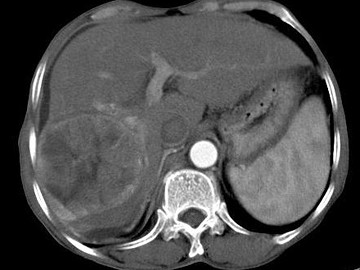

女,40岁,有口服避孕药史,肝区疼痛、腹部包块,AFP阴性,CT扫描如图,最可能的诊断是()

• A.肝细胞腺瘤

• B.肝再生结节

• C.结节性肝癌

• D.肝右叶巨块型肝癌

• E.肝黄色肉芽肿